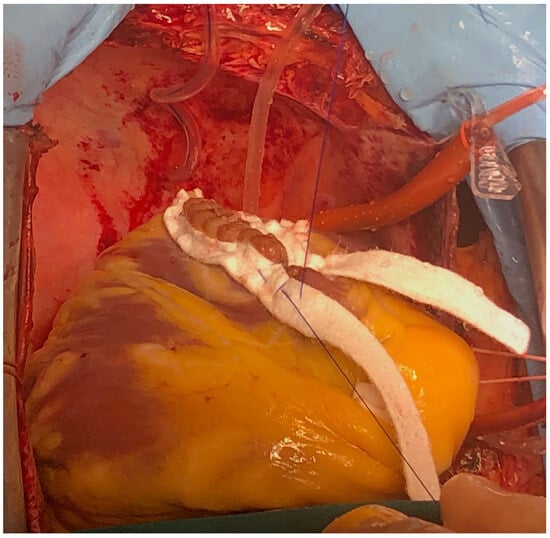

The surgery was carried out under general anesthesia, with iv induction and inhaled sevoflurane maintenance and total iv anesthesia during CPB. After median sternotomy, bicaval CPB was started, and the heart was arrested using anterograde and retrograde cold blood cardioplegia. After snaring both venae cava, the heart was enucleated with a 3.0 polypropylene stitch at the apex. A 10 cm incision was made on the posterior surface of the left ventricle, 2 mm parallel to the posterior interventricular artery. The margins of the VSD were identified. Interrupted matrass sutures of 2.0 Tevdek were placed circumferentially around the defect and used to secure a 4 × 7 cm bovine pericardial patch. The posterior papillary muscle was retracted into the sutures, so the mitral valve was replaced with a 27 biological prosthesis with preservation of the sub-valvular apparatus. The left ventriculotomy was closed with a double layer surjet suture, reinforced with Teflon felts. Details with surgical technique are shown in Figure 5, Figure 6, Figure 7 and Figure 8.

Figure 6. Surgical technique detail—large bovine pericardium patch.